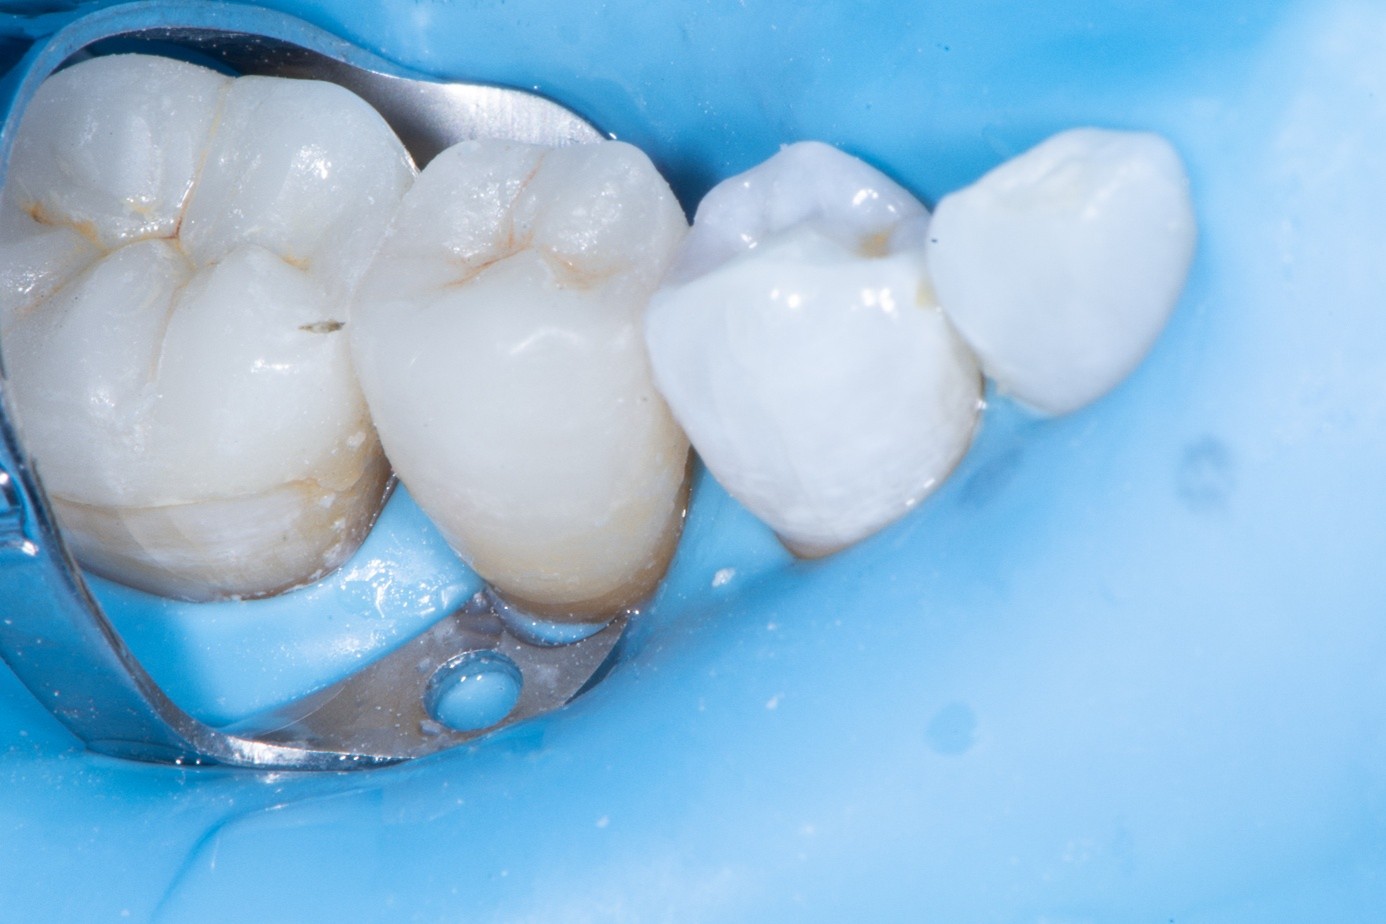

Case 2: Composite Facing Fracture

This case involved a patient with generalized mild anterior wear and an existing composite restoration on the maxillary left central incisor. The restoration extended from the middle third to the incisal edge and had excellent shade match and no marginal discoloration. The patient presented with a fractured central mesial portion of the composite (Figure 14 through Figure 16). Examination revealed a mixed failure pattern: Some adhesive and composite remnants remained on the tooth surface, while the fractured piece showed no residue internally. This finding suggested that the weak point was at the interface between composite and adhesive layer, with a minor cohesive component within the composite itself (Figure 17).

From a clinical standpoint, this pattern is reassuring, as it indicates a strong bond to the tooth substrate and that the restoration had functioned successfully until the composite material itself reached its fracture threshold. Considering the generalized wear pattern and patient history, parafunctional habits were suspected as the main cause of failure—the composite likely fractured when the applied functional stress exceeded its material strength.

Clinical Procedure

After achieving rubber dam isolation, the fractured composite segment was first air-abraded with aluminum oxide particles to clean and roughen the surface. It was then etched with phosphoric acid for 60 seconds, rinsed, dried, and treated with silane to enhance chemical adhesion (Figure 18 through Figure 20).8,9

The tooth surface was similarly air-abraded to remove biofilm and aged resin remnants, then selectively etched with phosphoric acid. Silane was applied intraorally to the exposed composite surface to promote bonding between the old and new composite layers.10 Following this, a universal bonding agent was applied to both the tooth surface and the fractured composite segment (Figure 21 through Figure 24).

Before light-curing, flowable composite resin was placed in the cavity, and the fractured segment was repositioned precisely into its original location. Heated packable composite was avoided due to thinness and brittleness of the fractured piece. Excess bonding and composite were carefully removed using a microbrush. The restoration was then polymerized from multiple directions to ensure optimal cure (Figure 25 and Figure 26). Finally, the restoration was polished and contoured to blend seamlessly with the surrounding tooth structure and adjacent composite (Figure 27).

Clinical Considerations and Tips

Air abrasion is crucial to remove the superficial, aged composite layer and expose fresh, bondable material.

Silane application on fractured composite surfaces improves chemical bonding and contributes to a stronger repair interface.

Flowable/injectable composite offers lower viscosity to avoid fracturing of such a thin fragment during placement.

Identifying parafunctional habits early is important—occlusal splint therapy may be indicated to protect the repaired restoration from fracture in the future.

The result was a seamless repair, preserving sound tooth structure and maintaining the excellent esthetic integration of the original restoration.

(14.) Intraoral view showing the fractured ceramic fragment positioned in place. The piece fits well, although minor gaps are present between the margins due to slight material loss, which can be restored using luting composite.

Figure 14

(15.) Intraoral view showing the fractured ceramic fragment positioned in place. The piece fits well, although minor gaps are present between the margins due to slight material loss, which can be restored using luting composite.

Figure 15

(16.) Intraoral view showing the fractured ceramic fragment positioned in place. The piece fits well, although minor gaps are present between the margins due to slight material loss, which can be restored using luting composite.

Figure 16

(17.) Mixed cohesive failure of the restoration, with a very small amount of adhesive remaining on the fragment, while the majority of the fractured surface shows fresh composite, indicating cohesive failure within the material.

Figure 17

(18.) The fractured composite fragment after sandblasting as a surface treatment, followed by etching and application of a single layer of silane, prepared for reattachment.

Figure 18

(19.) The fractured composite fragment after sandblasting as a surface treatment, followed by etching and application of a single layer of silane, prepared for reattachment.

Figure 19

( 20.) The fractured composite fragment after sandblasting as a surface treatment, followed by etching and application of a single layer of silane, prepared for reattachment.

Figure 20

(21.) Intraoral view after rubber dam isolation, showing prepared surfaces: both sandblasted and etched, with silanization applied only to the composite surface, ready for reattachment.

Figure 21

(22.) Intraoral view after rubber dam isolation, showing prepared surfaces: both sandblasted and etched, with silanization applied only to the composite surface, ready for reattachment.

Figure 22

(23.) Intraoral view after rubber dam isolation, showing prepared surfaces: both sandblasted and etched, with silanization applied only to the composite surface, ready for reattachment.

Figure 23

(24.) Intraoral view after rubber dam isolation, showing prepared surfaces: both sandblasted and etched, with silanization applied only to the composite surface, ready for reattachment.

Figure 24

(25.) Correction and removal of composite excess, followed by light polymerization.

Figure 25

(26.) Correction and removal of composite excess, followed by light polymerization.

Figure 26

(27.) Final intraoral view after complete polymerization under glycerin gel, showing a seamless repair with invisible margins, making the fracture line undetectable.

Figure 27